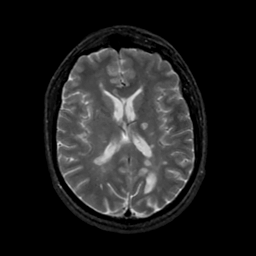

MR Study #17, July 7, 1991 -- Slice #29